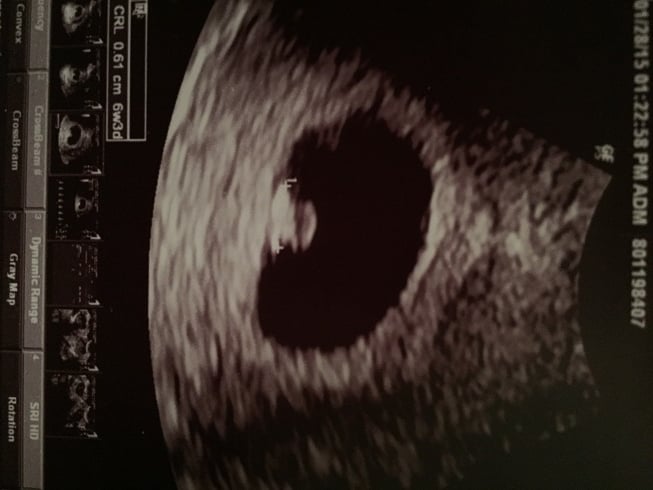

Thank you! So I am really confused...I understand that it's on the left side of the picture, but isn't that the right side of my uterus? That's how it was explained on a blog I read (see pic below...this is explaining for a transvaginal ultrasound). Can you help me understand? As I understand it, you are supposed to hold the picture to your belly upside down (to you, right side up to someone looking at you) and that will show you what side of your body it's on. So as I interpret it, it would be a boy...